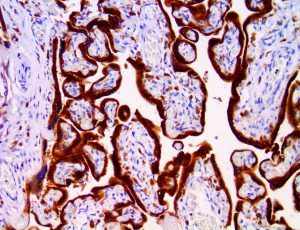

This activation induces inflammatory monocytes to highly express IL-6, starting a localized and then systemic cascade effect that results in hyperproduction of IL-6, which accelerates the inflammatory process. Because IL-6 also increases vascular permeability, excessive levels cause blood vessels to become very leaky. This, along with clotting factors released from vascular endothelial cells, stimulates the coagulation cascade, resulting in microthrombosis (tiny clots), which leads to ischemia and tissue death of the kidney, intestines, heart, liver, brain and extremities.